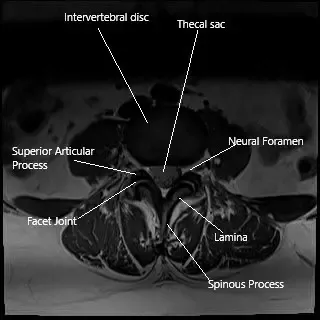

MRI axial section showing the facet joint.

Facet joints connect the vertebrae at the back of the spine and allow for smooth movement. They are surrounded by a capsule that produces synovial fluid—a lubricant that helps the joints move easily.

The facet joints are located behind each vertebra and guide motion in the spine. Each joint has smooth cartilage and is enclosed by a capsule filled with synovial fluid for lubrication.